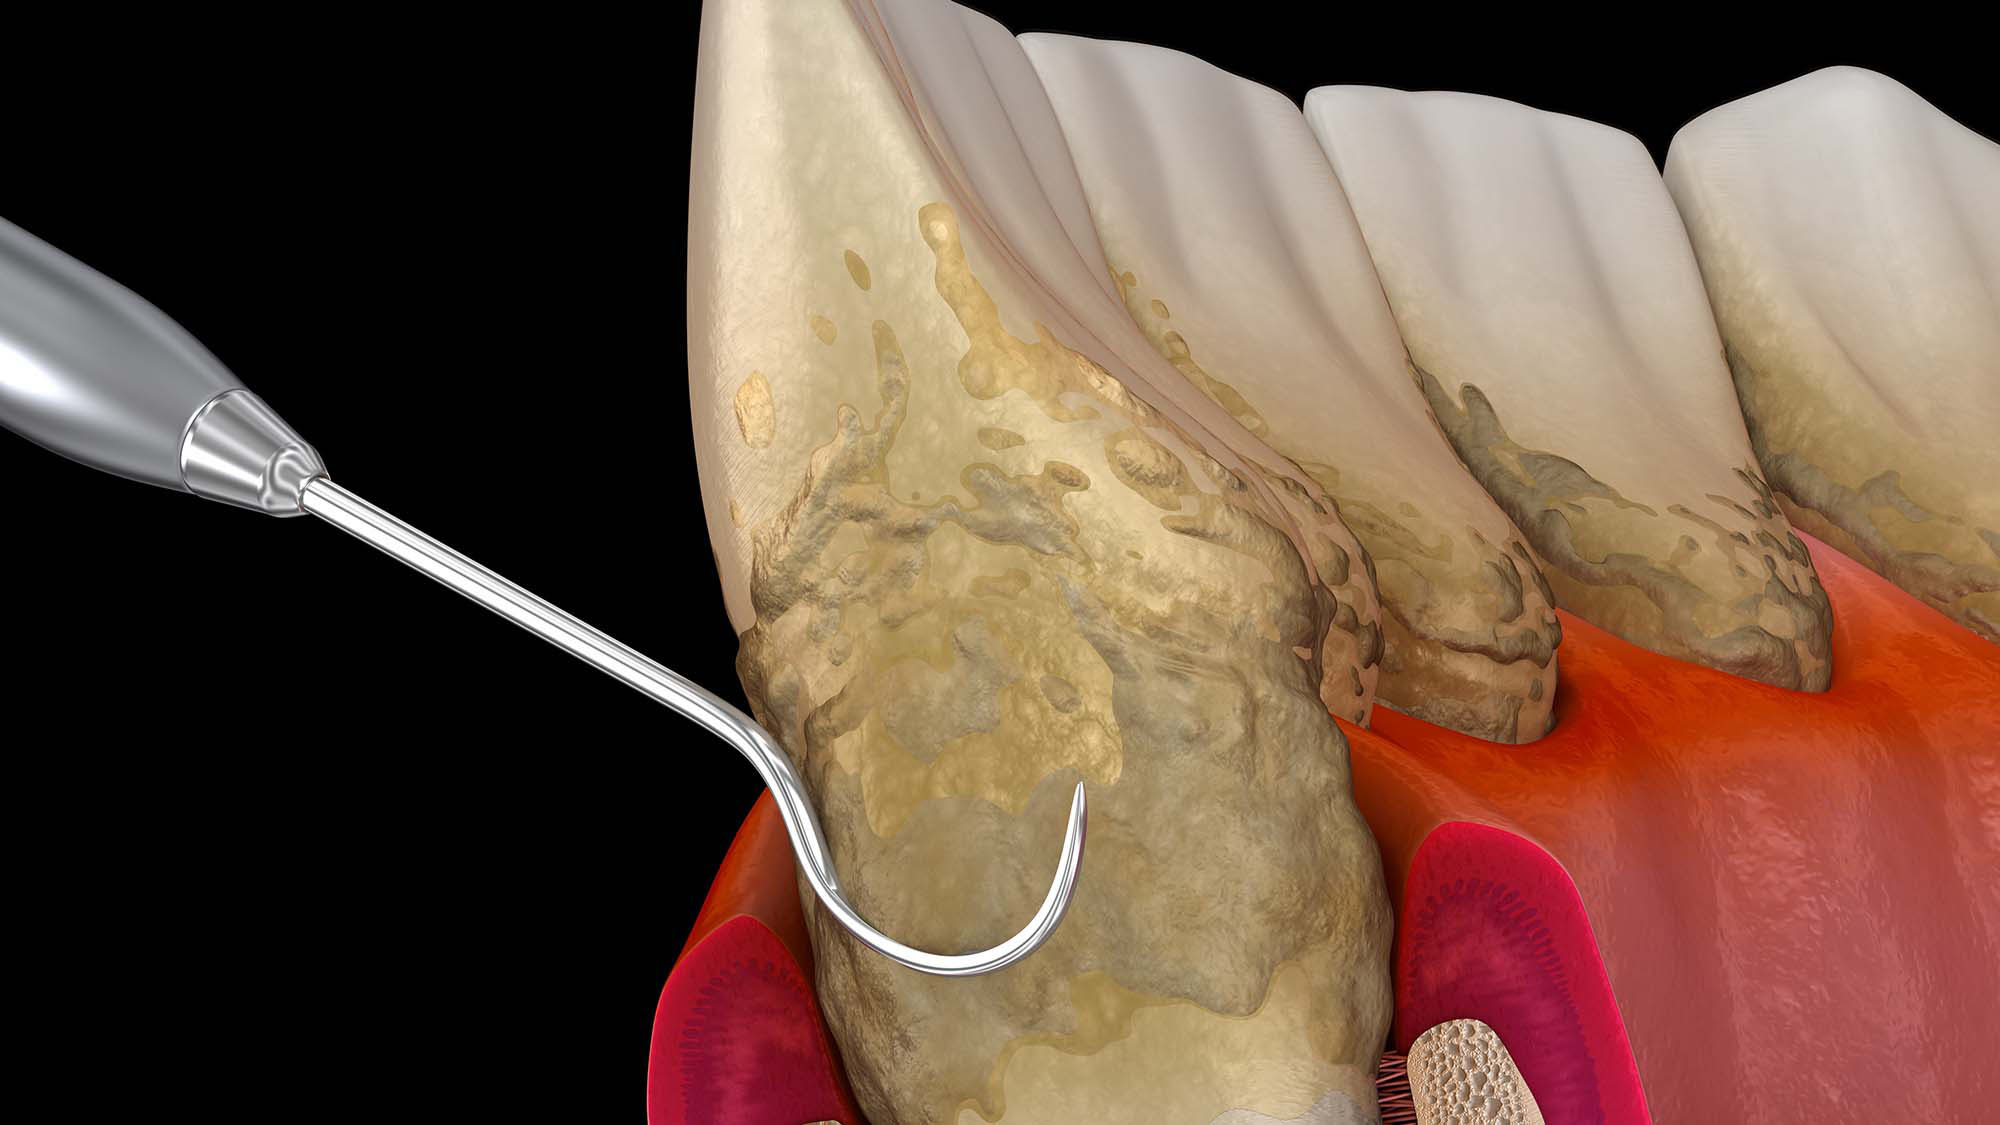

歯の根元のお掃除(ルートプレーニング)

歯周ポケット内部の歯根表面を清掃し、細菌の再付着を防止します。歯周炎の治療に必要な処置です。

04歯周ポケット内の清掃必要に応じて、歯肉の下の歯石や細菌を除去します